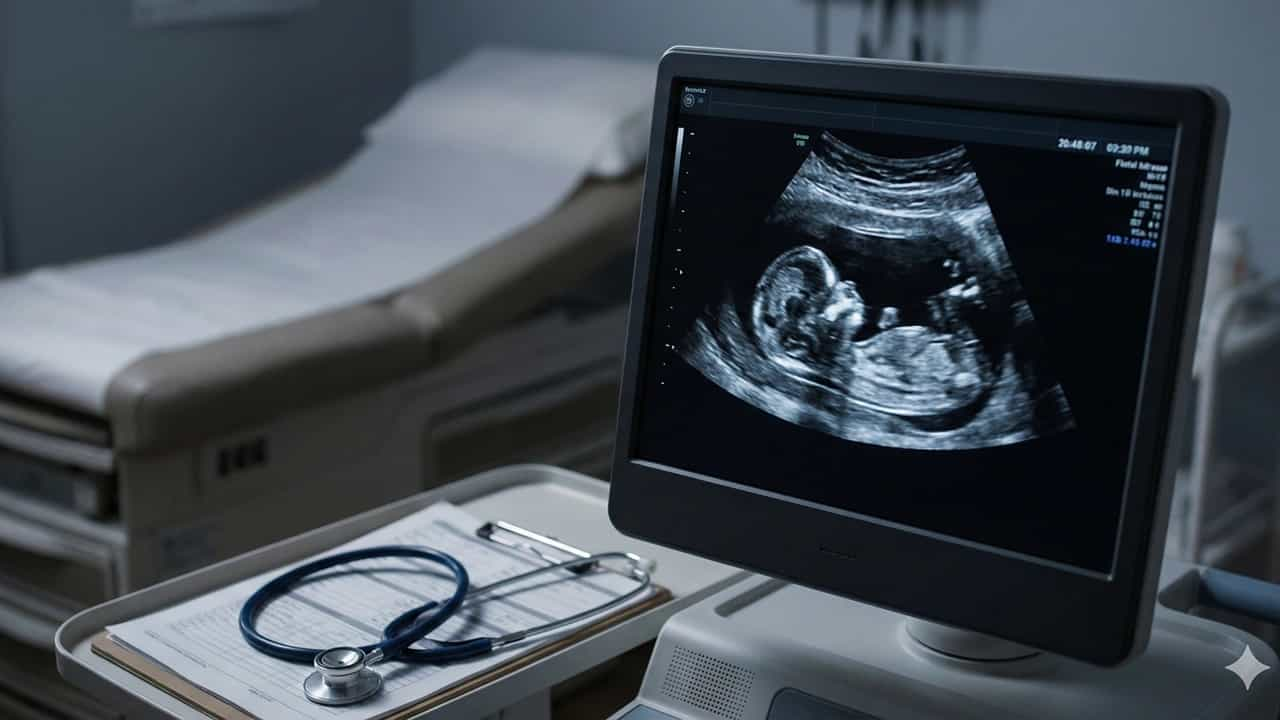

A Connecticut jury delivered a defense verdict on October 30, 2025, in a wrongful birth medical malpractice lawsuit filed by Lyanne Santos-Reyes against her obstetric care providers. Santos-Reyes alleged that Dr. Rachel L. Leonardi and Naugatuck Valley Women's Health Specialists failed to detect her daughter's spina bifida during prenatal ultrasounds in 2018, depriving her of the opportunity to terminate the pregnancy. The plaintiff claimed the August 2018 ultrasounds failed to properly visualiz...

A Connecticut jury delivered a defense verdict on October 30, 2025, in a wrongful birth medical malpractice lawsuit filed by Lyanne Santos-Reyes against her obstetric care providers. Santos-Reyes alleged that Dr. Rachel L. Leonardi and Naugatuck Valley Women's Health Specialists failed to detect her daughter's spina bifida during prenatal ultrasounds in 2018, depriving her of the opportunity to terminate the pregnancy. The plaintiff claimed the August 2018 ultrasounds failed to properly visualize the fetal spine, and she was never informed about incomplete anatomical views or offered additional testing. Her daughter was born with meningomyelocele, the most severe form of spina bifida, requiring lifetime care. The defendants denied all negligence claims, and the jury found in their favor on all issues.